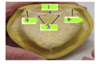

secondary stress bearing area of a md complete denture

crest of the residual ridge

classify the cross sectinonal ridge form

V-shaped